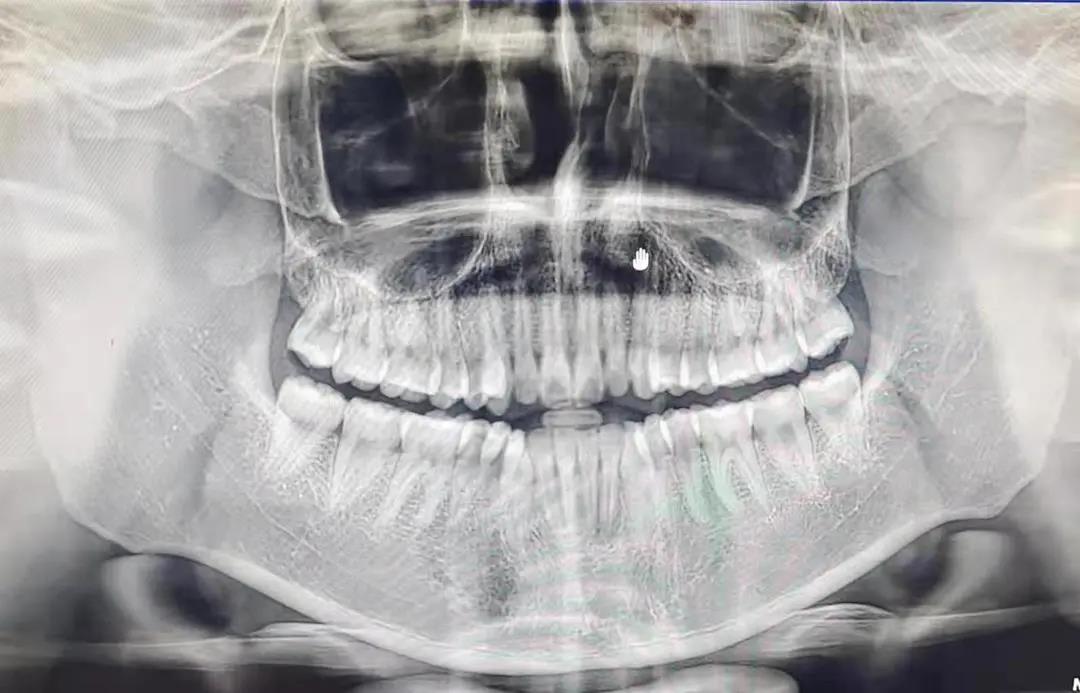

早上八点我们步行前往,到达时,给我们发了口罩、帽子。首先由冯雪老师给我们讲了目前国内外的口腔医学的发展形式,主要包括大学附属医院,口腔医院等。然后参观了院区,之后分组临床见习(正畸,综合,洁牙),正畸其操作精细,震撼,学到了各种操作器的用法和注意事项,然后去了影像室,给我的同学拍了片子,他的牙齿很好,最后进行了感控的基础知识教育,其中印象深刻的是器械的消毒灭菌的流程(回收~分拣~清洗~烘干~注油~打包~消毒~存放),了解到了感控的极其重要性!